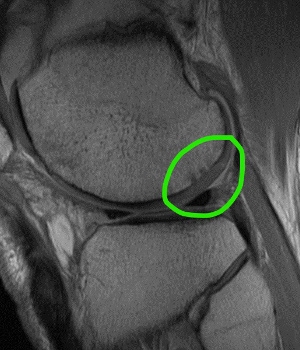

Before and After Image

Pre and Post Op MRI Showing Healed Cartilage Lesion